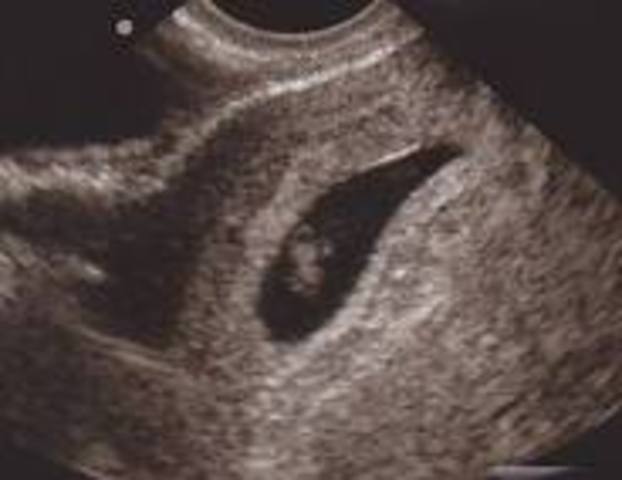

The baby's skin is transparent but the face is starting to look more human. Sex organs are being to form but the sex of the baby is still ahrd to determine. The baby is about the size of a lime.